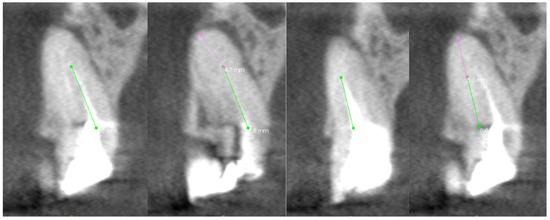

In the presented case, the patient was referred for repeated endodontic treatment due to periodic pain in tooth 16. The CT scans are presented in Figure 9. It shows underfilled canals and an inflammatory change in the periapical tissues. Treatment in rubber dam isolation under microscope magnification began with the removal of the composite cement from the tooth chamber. The mouths of three canals were located. The palatial and mesial buccal canals were cleared. Patency of the distal buccal canal was not obtained. Despite the use of a surgical microscope, due to the curvature of the canal, the cause of the obstruction was not determined. Thus, computed tomography images, which are shown in Figure 9, enabled the identification of a broken file in the apex of the root, the fragment of which extends beyond the apical foramen. There is a high probability of pushing a broken instrument into the maxillary sinus if an attempt is made to remove it. Based on these CT scans, a 3D model of the tooth with marked canals and a broken file was created. The resulting hologram could be enlarged, reduced, and rotated. Thanks to the ability to assess the curvature of the canal simultaneously in three spaces and the position of the broken instrument, it was possible to adjust the appropriate tool to bypass it. An ultrasonic tip was used on which a Miller probe was mounted. The tip of the tool was bent at an appropriate angle and inserted along a specific path after analyzing the hologram of the distal canal. This was made possible by combining real-world images (Miller’s needle) with digitally generated virtual objects, namely, 3D tooth holograms, as in Figure 10. As in the first case, Table 3 shows the percentage share of individual CT scans in the visualization of the entire path of each root canal.

Figure 9. The CT scan of the tooth was used for the analysis of the root canals in the transverse plane, in the case of tooth 16, where the yellow line denotes the axial plane, and the green line denotes the longitudinal plane.